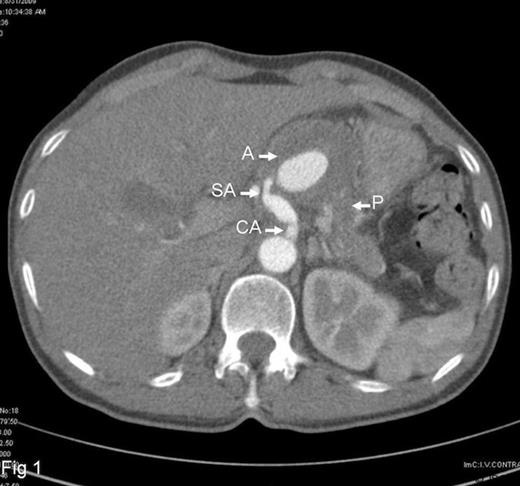

A 60-year-old male was referred with history of repeated epigastric pain and malena. The pain was intense, radiated to the back and, on occasion was associated with profuse sweating and fainting attacks. In the preceding four months, he had 5 such episodes of pain and malena. These attacks were characterized by malena occurring a few hours after the onset of pain and were associated with transient elevation of serum amylase and lipase. He was a known hypertensive on regular medicines and denied any history of alcohol consumption. During the last episode of bleeding, his hemoglobin had dropped to 3.5gms/dl requiring 8 units of blood transfusion. Upper GI endoscopy performed on three occasions showed bleeding from the second part of the duodenum, but the source of bleeding remained obscured. Colonoscopy at the time was unremarkable. In view of suspected pancreatitis, abdominal ultrasonography was performed, which revealed a hypo-echoic lesion near the head-neck junction of pancreas. On contrast CT scan, this lesion turned out to be a partially thrombosed 7cm aneurysm close to an otherwise normal pancreas (Fig.1). The 3D-CT reconstruction clearly demonstrated the origin of the aneurysm to be from the splenic artery (Fig.2). To stem further bleeding, a coeliac axis angiography followed by micro-coil embolisation of splenic artery was performed.

Contrast CT shows partially thrombosed splenic artery aneurysm. ( A =aneurysm, SA =splenic artery, CA =celiac artery, P =pancreas)